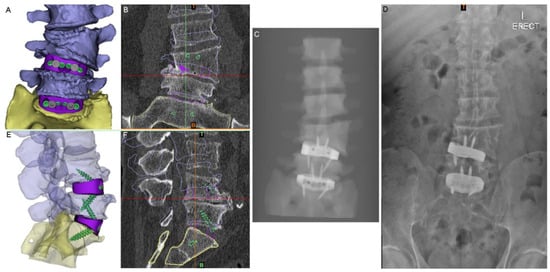

Figure 3.

Virtual surgery planning (VSP). (A) Anterior view of the 3D model of the planned anatomical reconstruction and cage positions for medium-sized cages (NB: a small cage was actually used at the L4-5 level). (B) The 3D model shown in (A) superimposed on S1 in the preoperative CT (coronal slice shown). (C) Simulated X-ray of the 3D model in (A). (D) Postoperative standing X-ray. (E) Lateral view of the planned reconstruction with translucent vertebrae to show the screws and devices. (F) Sagittal-plane CT slice with the 3D reconstruction shown in (E) superimposed on S1 to show the planned postoperative state compared to the pathological state.

The PSIs were designed using 3DMorphicCAD (3DMorphic Pty Ltd., Sydney, Australia) and Rhinoceros (vs6, McNeel and Associates, Seattle, WA, USA) [22]. Features incorporated included: radiographic alignment assessment features, anti-expulsion teeth, integral screw fixation, variable surface topology/porosity, large central graft window for auto/allograft, pre-planned screw lengths and trajectories (Figure 3), as well as contacting surfaces designed to match the superior and inferior endplate morphologies of each (L4-5 and L5-S1) of the interbody spaces and to correct vertebral alignment in both coronal (scoliotic) and sagittal (lordotic) planes.

Imaging at day 1 postoperatively demonstrated excellent implant positioning (Figure 6). Disc and neuroforaminal height correction, as well as lordotic and partial scoliotic correction closely matched the planned correction in the VSP. At 9-month postoperative imaging, implant positioning and parameter corrections were stable. Early radiographic evidence of bony fusion at both operative levels and osteophyte resorption were appreciable (Figure 7).

The close adherence of the relative implant and anatomy positioning in postoperative imaging to the preoperative VSP demonstrates the accurate realisation of VSP correction goals and the validity of this technique (Figure 6). The ability to assess the vascular anatomy preoperatively and refer to the VSP intraoperatively allowed the surgical team to be better prepared, particularly in dealing with the extensive adhesions at the aortic bifurcation, and more rapidly successfully manage the intraoperative aortic tear [8]. The use of prominent osteophytes as patient-specific pathoanatomical landmarks also aided surgical navigation.